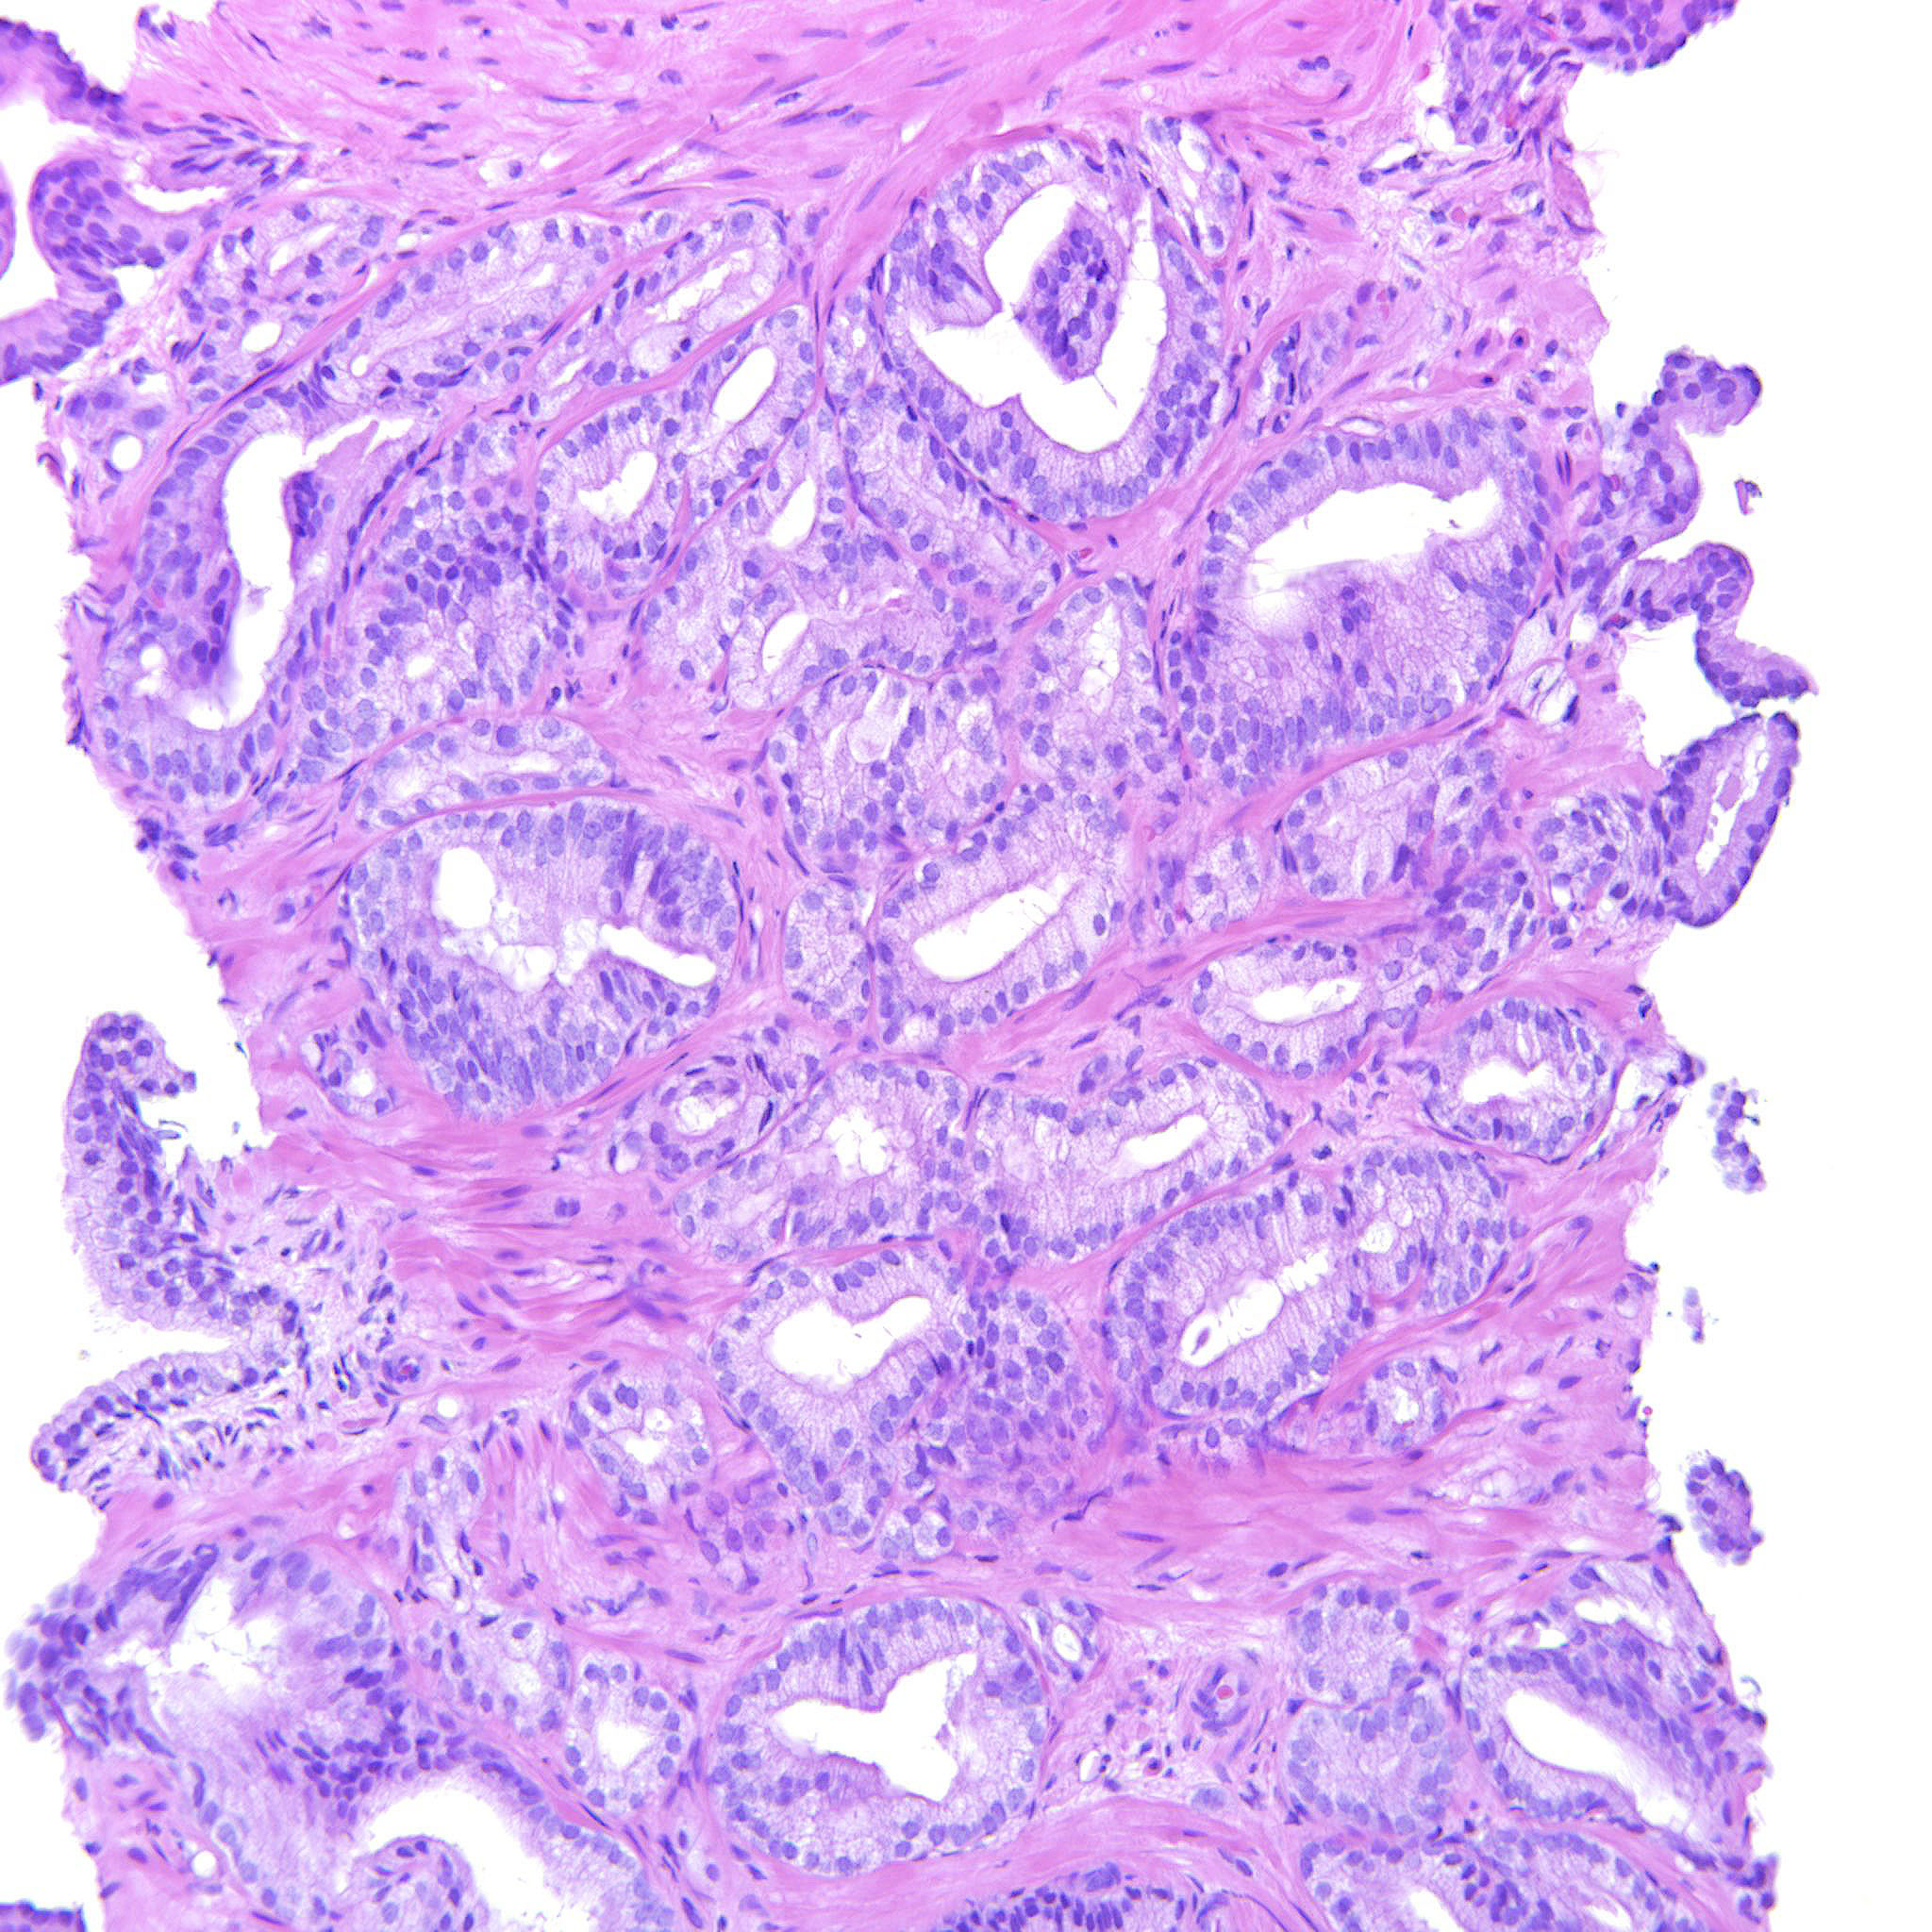

Consensus grade: GS 3+4=7 (ISUP 2)

Case description (by case creator):

Some images only contain GP3 but there are also areas with poorly formed and fused glands justifying 347.